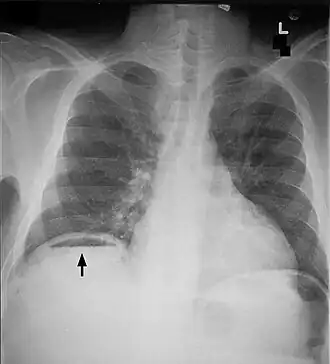

«Симптом серпа» под правым куполом диафрагмы | |

Симптом серпа (симптом полумесяца) — радиологический признак некоторых заболеваний, выявляемый при рентгенографии и компьютерной томографии. Представляет собой серповидный участок просветления, являющийся отражением скопления газа вокруг органа или патологического образования[1].

Симптом серпа, выявляемый между правым куполом диафрагмы и печенью при исследовании органов брюшной полости — признак перфорации полого органа брюшной полости (желудка или кишки), связан с поступлением газа в брюшную полость.